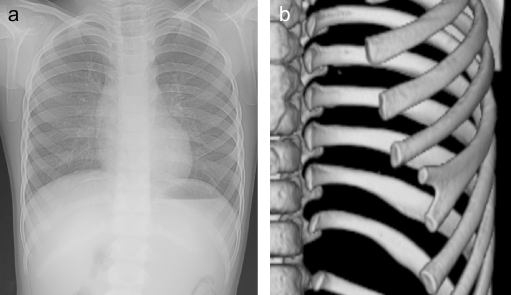

Individuals with Gorlin–Goltz syndrome often display skeletal abnormalities, most notably:

• Bifid Ribs: A common finding where ribs are forked or split.

• Vertebral Anomalies: These can range from minor deformities to significant issues that impact spinal integrity.

Understanding these skeletal variations is essential for proper diagnosis and orthopedic management.